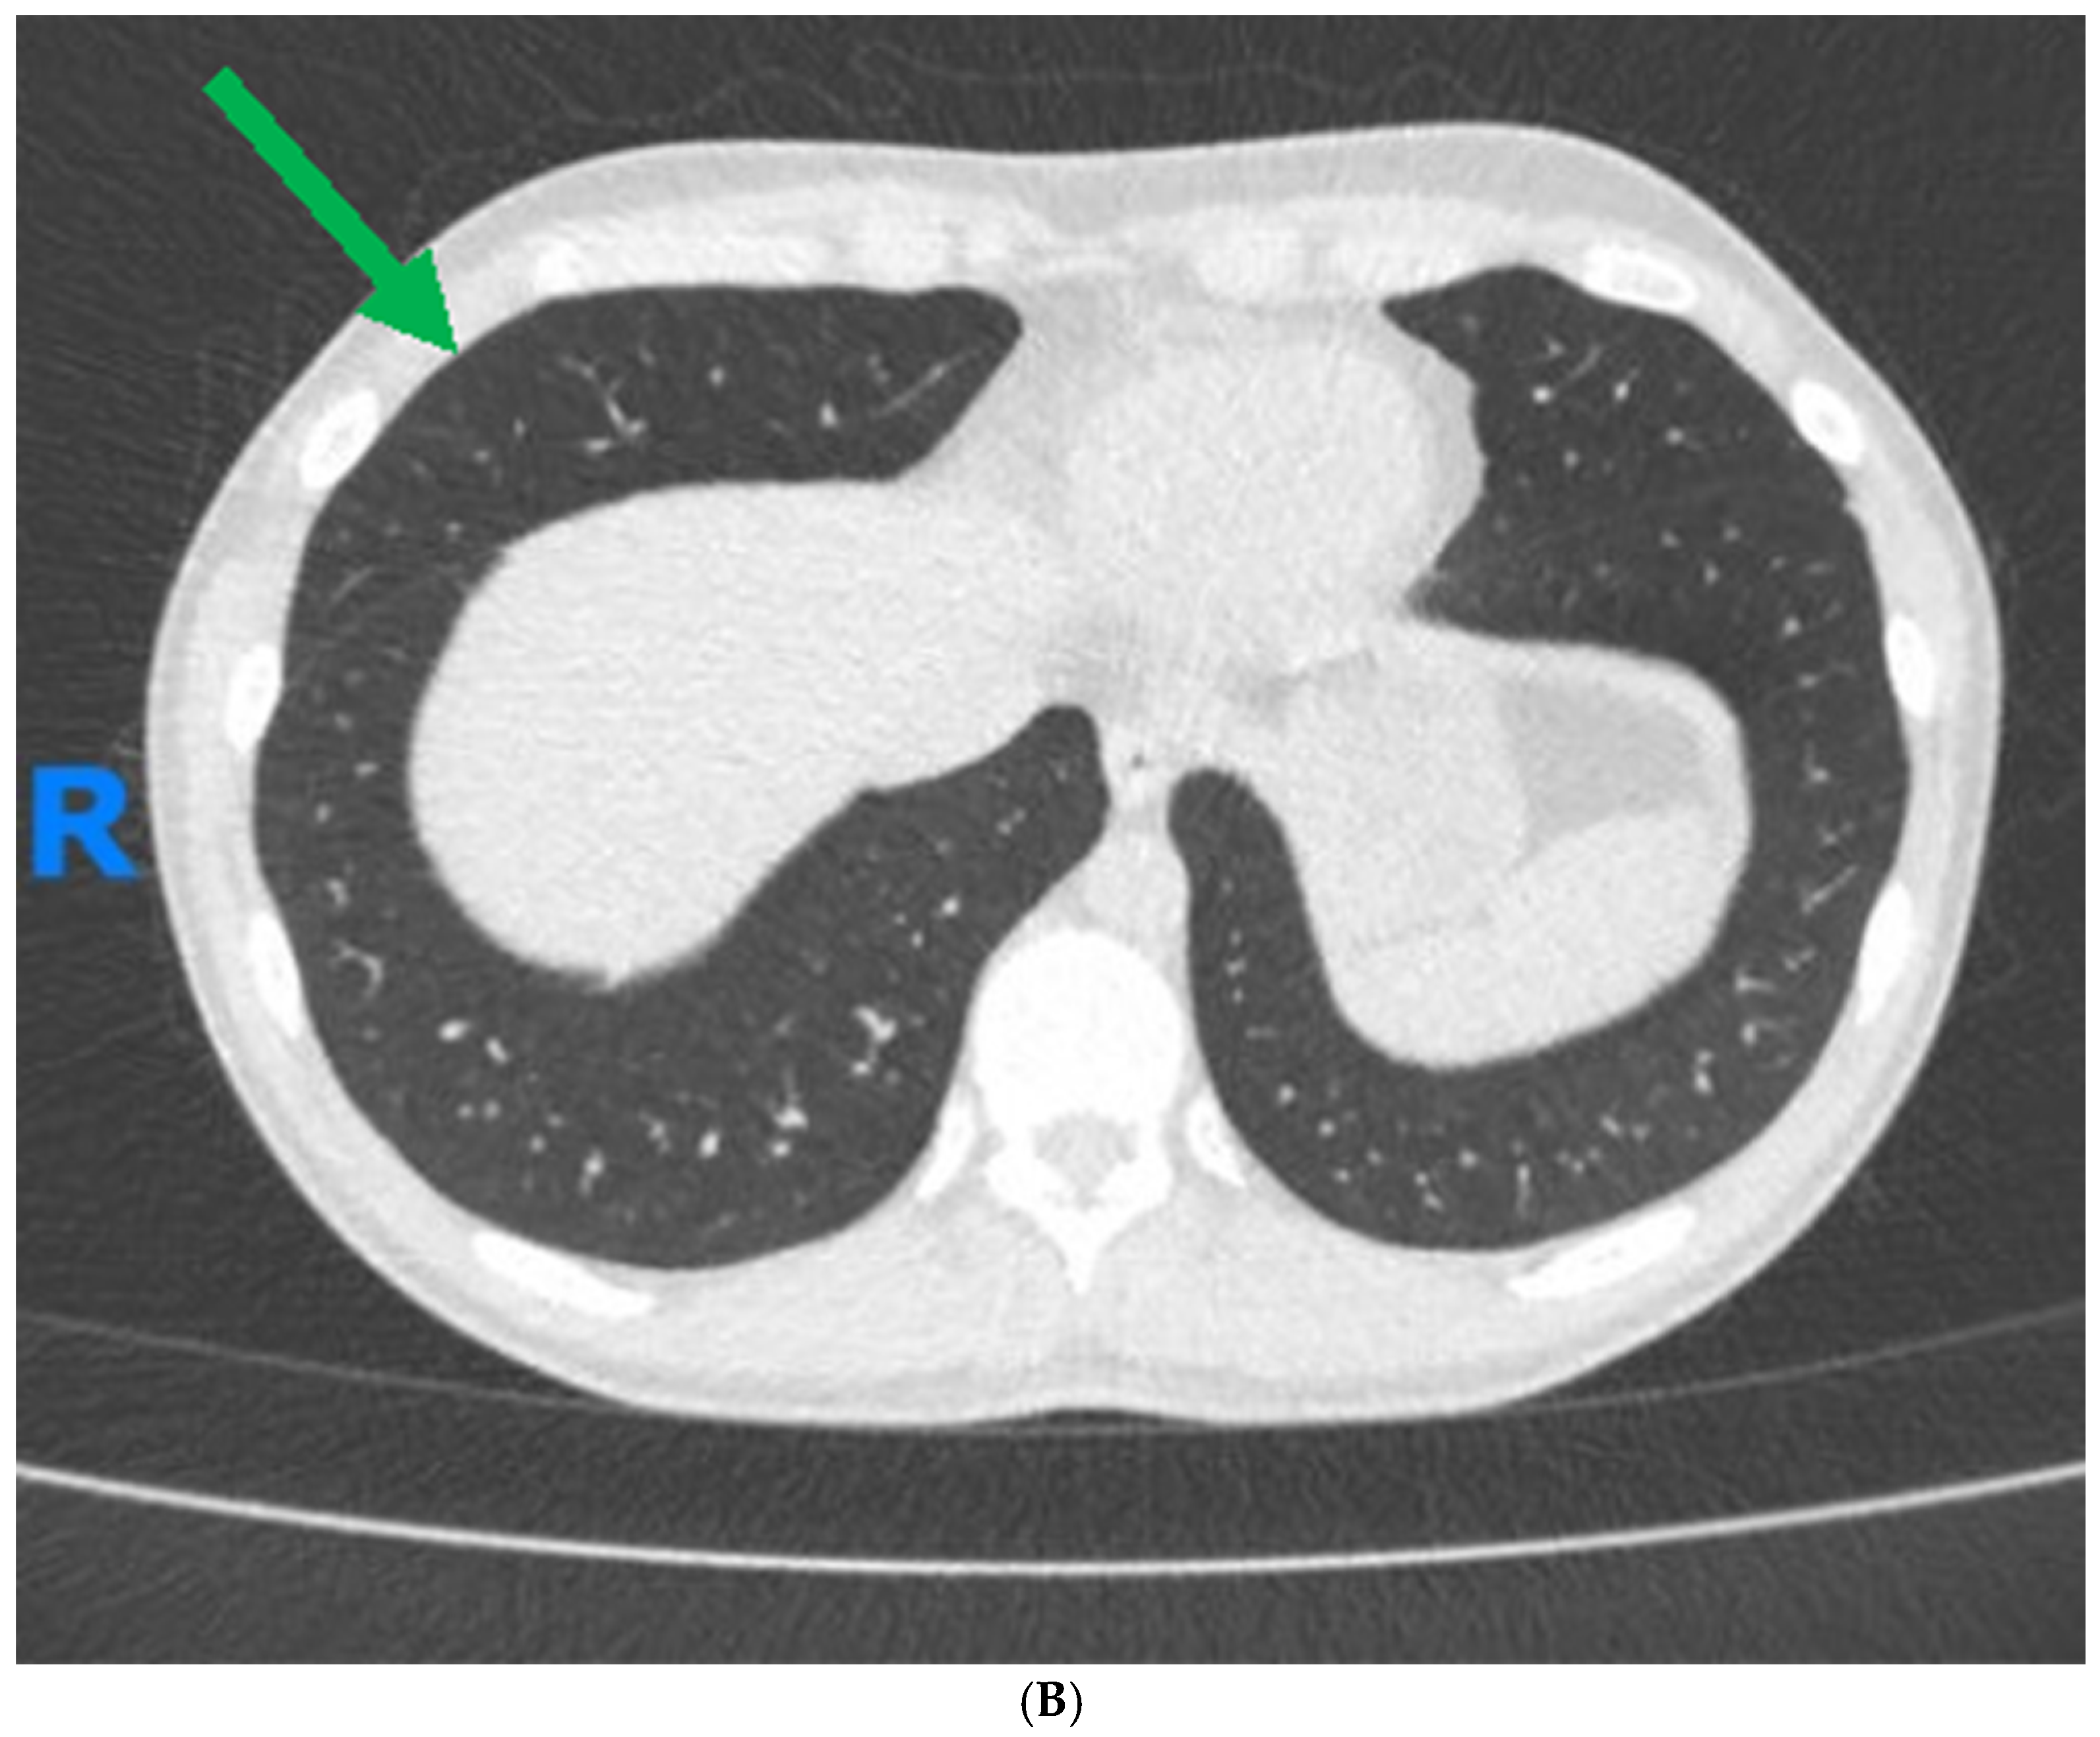

1. Case Report

| High-resolution computed tomography | More sensitive than X-ray, can identify features such as bronchial wall thickening, airway dilation, and mucoid impaction that are indicative of bronchiectasis, tree-in-bud patterns, ground-glass opacities, or honeycombing indicative of fibrotic changes [74,75]. |